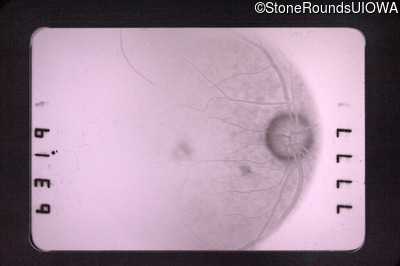

Fluorescein Angiography - Right - 20/30

Exemplar